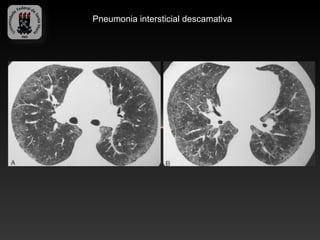

-PNEUMONIA INTERSTICIAL DESCAMATIVA

-3% das DPI

-Afeta fumantes jovens de 30 – 40 anos

-2H:1M

-Histologicamente: grande número de macrófagos intra alveolares e

infiltrado inflamatório intersticial

-Radiografias habitualmente normais

-Achados TC

-   Opacidades em vidro fosco bilaterais e difusas com predomínio

inferior

-   Faveolamento é raramente visto.

Pneumonia intersticial descamativa